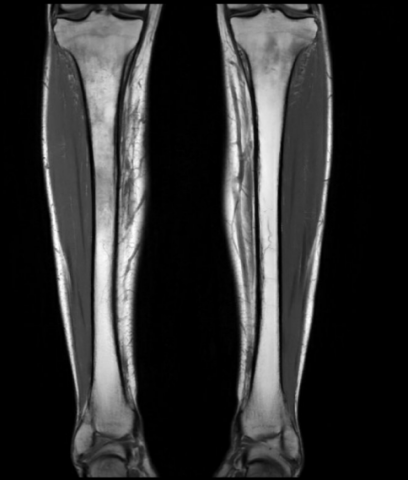

Séquence coronale.png

Séquence coronale DP FS montrant un oedème méd

ullaire tibial bilatéral, plus prononcé à droite, avec

réaction périostée.